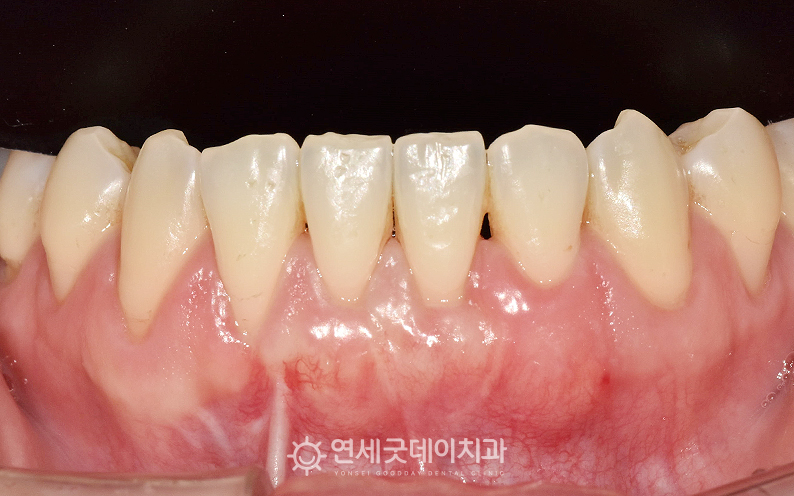

● 담당과 : 교정과 + 치주과 아랫니의 잇몸퇴축으로 내원해주신

아래 앞니 부위의 잇몸퇴축이 뚜렷하게 관찰됩니다.

측면에서 보면 다른 치아들에 비해 #31 부위의 이러한 구조적 문제를 개선하기 위해 ❏ Option 1. 부분교정 후 잇몸이식수술 (치주교정) 환자분께서는 근본적인 해결 방법인 1번 방법을 선택하셨으며 약 8개월 간의 부분교정을 마친 모습입니다. 순측으로 경사졌던 치아가 올바른 위치로 이동하였으며 이후 하악 전치부의 잇몸을 전반적으로 보강하기 위해